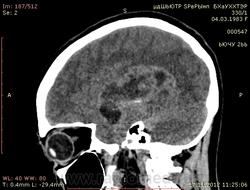

Молодая женщина, 29 лет. Обратилась на прием к неврологу 26.10.12г с  болями в шее, назначено лечение амбулаторно по сосудистой головной боли, остеохондрозу.. После 14.11.12г обратилась к другому неврологу повторно, 16.11.12г направлена в стационар. Жалобы: на снижение зрения, головные боли, головокружения, слабость, повышение температуры. Провели СКТ головного мозга натив и контрастирование. Подскажите пожалуйста, коллеги- Это опухоль? тогда какая (глиобластома, невринома, менингиома?) и локализацию. Спасибо.

Нативное исследование.

Одно можно сказать точно: это не менингиома и не невринома (у тех структура однородная). Это Вам в помощь http://www.radiologyassistant.nl/en/p47f86aa182b3a/brain-tumor-systematic-approach.html

Мне кажется, что тут субэпендимарная глиома. Указываете степень дислокации, накопления и к нейрохирургам.

Согласна с Андреем Юрьевичем. Все остальное возможно, в том числе олигодендроглиома. Впрочем не принципиально. К нейрохирургам!

Только что узнала результаты вскрытия.Гистология пока не готова.

Глиобластома с прорастанием стенки правого бокового желудочка, выраженный отек, смещение срединных структур, вклинение миндалин мозжечка в БЗО.